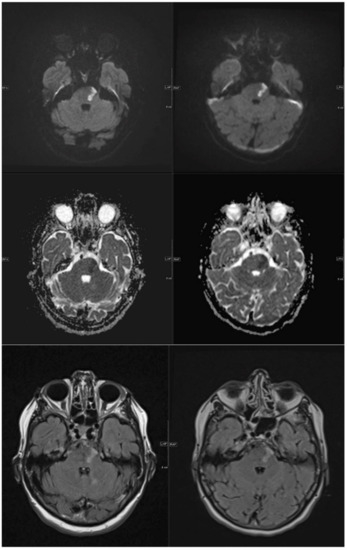

| Patient 5 | 58 | facial droop, hemiparesis right side | 10 | S | multiple subacute infarcts posterior circulation on both sides | 40 | 1050 |